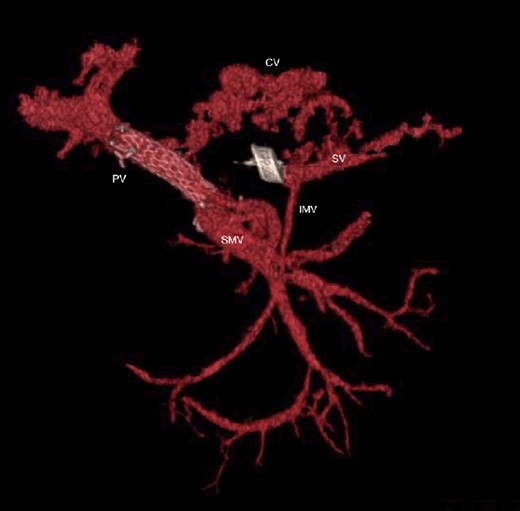

The abdominal exploration was difficult due to significant inflammatory adhesions, which can be attributed to the presence of a pancreatic fistula and the delay of relaparotomy. There was no bleeding observed within the abdominal cavity, and no bleeding was seen from the multitubular drain during the exploration. We hypothesized that the bleeding was of venous origin caused by drain-induced recurrent erosion of peripancreatic vessels, resulting in intermittent bleeding, and that removing drains could help in attaining venous hemostasis. As a result, it was decided to remove the drains. However, this resulted in a significant hemorrhage via the drain orifice. Due to failure to identify the exact origin of bleeding and without the possibility of completion pancreatectomy, we performed a damage control procedure by packing through the drain orifice. This successfully stopped the bleeding. A postoperative CT scan located the packing sponges anterior to the spleno-mesenteric confluence (SMC) (Fig. 2). A percutaneous transhepatic portography showed an irregular aspect of the SMC, without thrombi or contrast extravasation (Fig. 3). After consulting with the interventional radiology team, we placed a cover stent (Fluency™ Bard, Murray Hill, USA) in the SMC (Fig. 4). Two days later, we removed the packs, and a massive hemorrhage recurred, necessitating a new packing. The stent was not seen on a subsequent CT scan. We then performed an endovascular procedure to exclude the segment of the irregular SMC. An Amplatzer™ vascular plug (Abbott Vascular, Santa Clara, USA) was placed in the splenic vein, extending distally to just surpass the inferior mesenteric vein (IMV) insertion (Fig. 5). A cover stent was subsequently deployed in the portal vein, extending distally to the superior mesenteric vein. This allowed for the exclusion of the splenic vein segment that lies between the inferior mesenteric vein insertion point and the spleno-mesenteric confluence (Fig. 5). The packing sponges were removed 10 days later without bleeding recurrence, and the patient finally showed clinical improvement. After 3 years, the stent was visible and permeable on a follow-up CT scan. The scan showed development of venous collaterals, which drain the distal splenic vein and inferior mesenteric vein through the lesser omentum (Fig. 6).

CT scan at 3 years, with development of venous collaterals that drain distal splenic vein and inferior mesenteric vein through the lesser omentum. PV portal vein, SMV superior mesenteric vein, SV splenic vein, IMV inferior mesenteric vein, CV collateral veins.